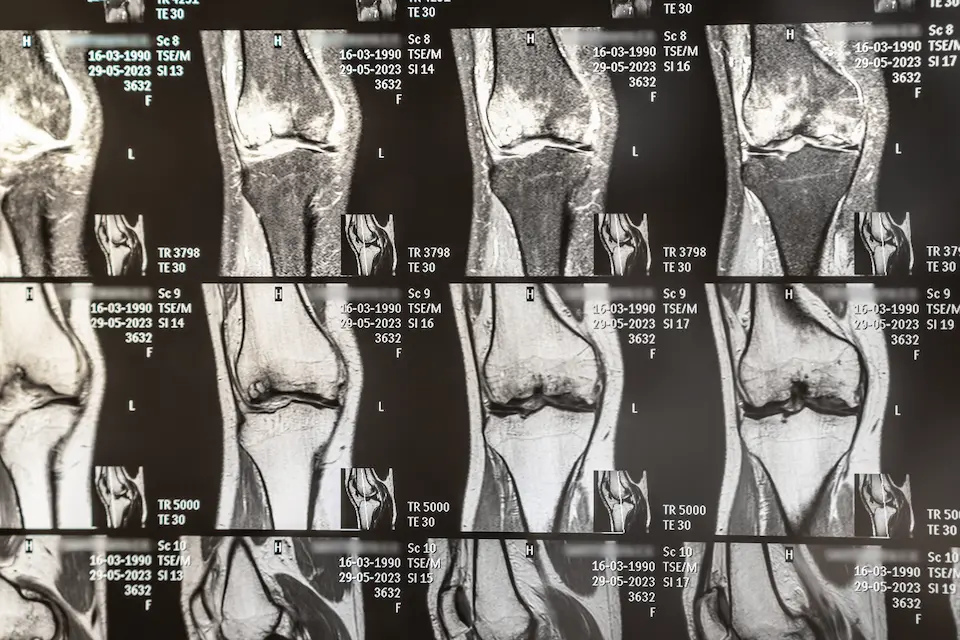

MRI検査

半月板損傷が疑われる場合は、病院でMRI検査を行い損傷の有無だけでなく、断裂のタイプや程度(グレード)まで詳しく検査する必要があります。

半月板損傷のグレード(Mink分類)

半月板がどのくらい損傷しているかは、MRIを使って詳しく調べることができます。損傷の程度を4つの段階(グレード)に分けて診断されます。

- グレード0:正常

半月板の中に異常な信号はなく、健康な状態です。 - グレード1:初期の変性

半月板の内部に斑状の高信号が見えますが、表面までは達していません。 - グレード2:やや進んだ変性

半月板の内部に線状の高信号が見えますが、まだ表面までは達していません。 - グレード3:断裂している状態

・3A:線状の高信号が表面まで達しています

・3B:不規則な形の異常が表面まで達しています